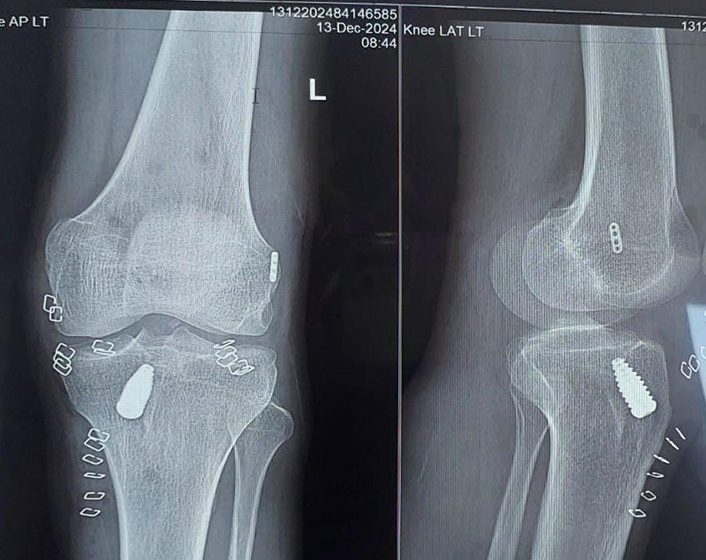

ACL Ligament after Surgery

ACL (Anterior Cruciate Ligament) injury treatment varies based on the injury’s severity and the patient’s lifestyle. For minor tears, non-surgical treatments like rest, physical therapy, and bracing and some times internal bracing may suffice to restore knee stability and function. Physical therapy focuses on strengthening the muscles around the knee, improving flexibility, and regaining balance. For severe tears or active individuals, surgical reconstruction is often necessary. The surgery involves replacing the damaged ligament with a graft, typically from the patient’s own tissue. Post-surgery rehabilitation is critical, involving a structured physical therapy program to ensure proper healing, restore full range of motion, and regain strength.